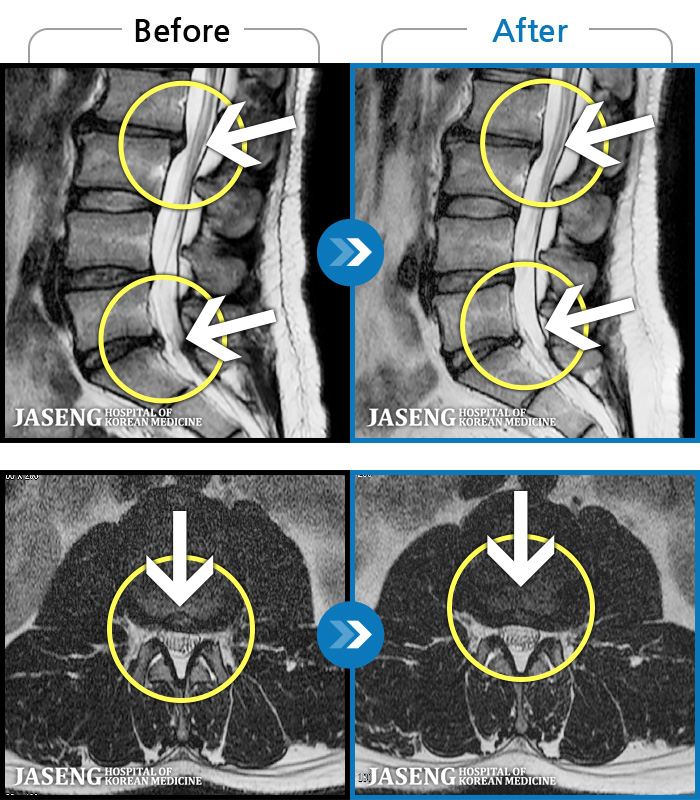

1,240 MRI ũ ʸ Ȯϼ.